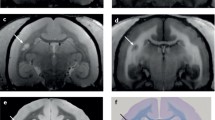

Central vein imaging is a promising technique to increase the specificity of MRI and was the topic of a recent Consensus Statement by the North American Imaging in MS (NAIMS) Cooperative [19]. That WM MS plaques form around venules was described pathologically over 100 years ago [20]. Susceptibility-based MR techniques (e.g., phase imaging, T2*, quantitative susceptibility mapping) are highly sensitive to iron and can be used to demonstrate the presence of a central vein within a T2-hyperintense lesion (Fig. 3.2a, b). One method with particular promise is FLAIR* [23], which combines 3D FLAIR and 3D T2*-weighted images in the post-processing setting (after they have been acquired). FLAIR* leverages the high sensitivity of FLAIR to demonstrate WM lesions, combined with the ability of T2* to detect blood vessels. Currently, FLAIR* is available on some commercial scanners, with increased availability across multiple MR manufacturers expected in the near future.

T2*-weighted image acquired at 7T demonstrating a hypointense central vein (arrow) on magnitude (a) and phase images (b). On phase images, a hypointense rim around the periphery of the lesion is also seen, which may suggest the presence of iron-laden microglia at the periphery of the demyelinating plaque. (c) High-resolution T2*-weighted image acquired at 7 T in axial plane showing an intracortical (Type 2) lesion (arrow). Source images in this figure were previously published and [21 (Panels A and B), 22 (Panel C)] and are used with permission

Cortical lesion detection may offer another approach to increase the specificity of MRI for CNS demyelination. Cortical lesions were described on histopathology several decades ago [27], but their clinical significance is not known due to difficulty visualizing them with current MR technology. Histopathologically, they are classified into Types 1, 2, and 3 (leukocortical, intracortical, and subpial, respectively) [28]. Subpial lesions are thought to be the most common, may span several gyri, and may be extensive, particularly in progressive MS [29]. Visualization of all three subtypes has been challenging, but particularly subpial lesions, which remain essentially undetected at conventional field strengths (1.5 and 3T). Multiple reasons for these challenges exist, including partial voluming from adjacent CSF, the small size of cortical lesions within an already thin cortex of 2–3 mm (which is often below the resolution of typical clinical images), and their relative lack of MR contrast due to their paucity of inflammation. Emerging MR techniques at higher resolutions and field strengths (7T) can generate better tissue contrast and may offer better visualization of these lesions (Fig. 3.2c). Recent work at 7T has described subpial lesions in the postmortem setting [30, 31]. However, translating this in vivo will require a clinically feasible scan time, which remains a challenge. Like central vein imaging, once cortical lesions can be reliably detected, further studies will be needed prior to implementation into routine clinical care to determine sensitivity and specificity prospectively in patients who present with typical demyelinating syndromes, and in clinical scenarios with nonspecific/atypical symptoms and/or MRI findings.